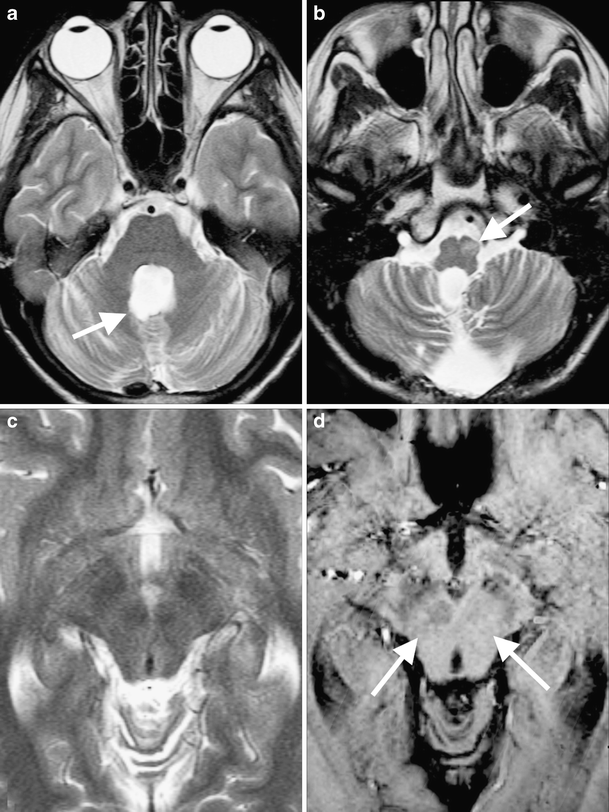

Red nucleus degeneration in hypertrophic olivary degeneration after Red Degeneration In Medical Term In macular degeneration, the center of the retina begins to deteriorate. As we age, it's important to get regular eye exams to check for a condition called macular degeneration. (29,30) red degeneration describes the hemorrhagic necrosis of a rapidly enlarging fibroid due to venous thrombosis of peripheral vessels. Amd is the most common cause of severe loss of eyesight among. Red Degeneration In Medical Term.